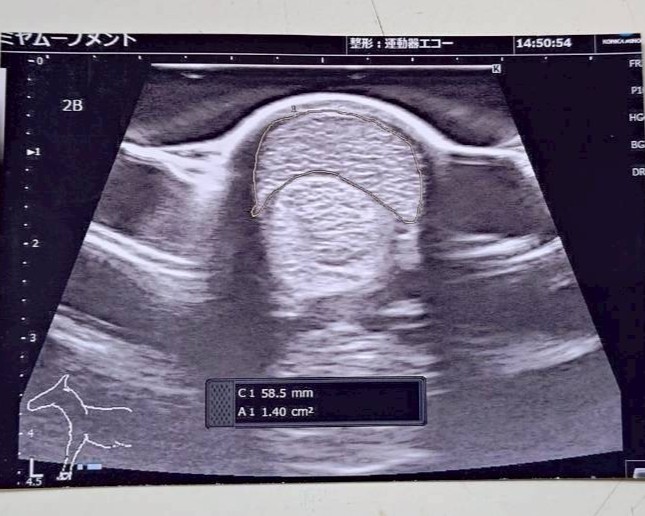

なお前走後に両前肢のエコー検査を行ったところ、腱に損傷は見られないものの腱が太くなっているので注意が必要との診断でした。